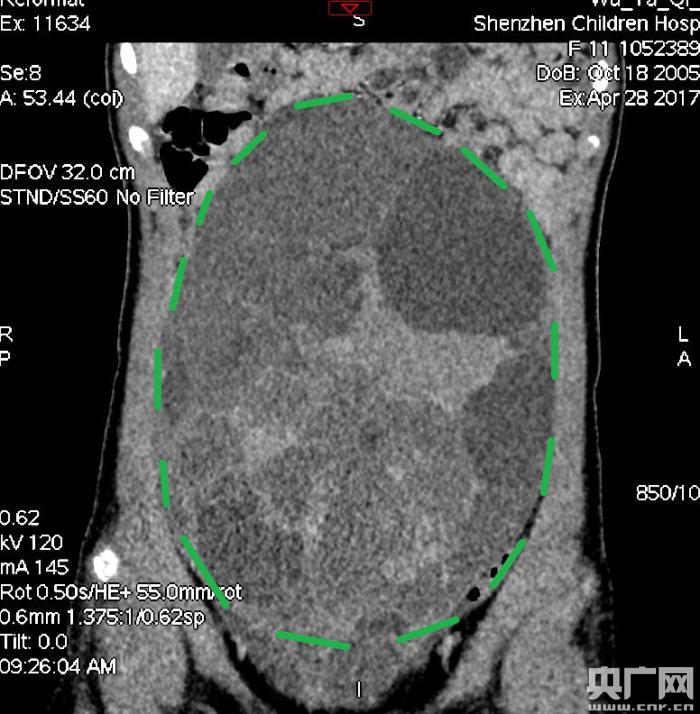

入院后,普外一科肖東主任向家長詢問了病史,仔細(xì)進(jìn)行了體格檢查,并完善腹部CT。CT結(jié)果提示,孩子的大部分腹腔、盆腔被一個(gè)巨大的腫瘤占據(jù),腸道、血管和腎盂都受到了不同程度的壓迫。從CT上看,腫瘤很可能起源于左側(cè)的卵巢。

手術(shù)中發(fā)現(xiàn),小琪腹中的腫瘤體積巨大,大小約為25×20×15厘米,表面光滑,來源于左側(cè)卵巢。醫(yī)生們首先將其與周圍的組織小心剝離,然后將這個(gè)占據(jù)孩子腹腔、盆腔大部分的巨大包塊完整切除,切除腫瘤后還重建了左側(cè)卵巢。剖開瘤體,發(fā)現(xiàn)瘤體為囊性及實(shí)性混合組成,瘤體內(nèi)部充盈著粘液狀的液體,重量達(dá)到了3000克。術(shù)后小琪病情穩(wěn)定,測量腹圍從術(shù)前的72厘米減小到了62厘米。